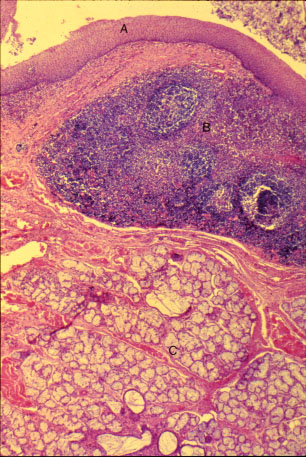

K-slide 54: Still higher magnification of slide 52

A. Stratified squamous epithelium

B. Lymphatic tissue (diffuse and nodular)

C. Mucous tonsillar glands